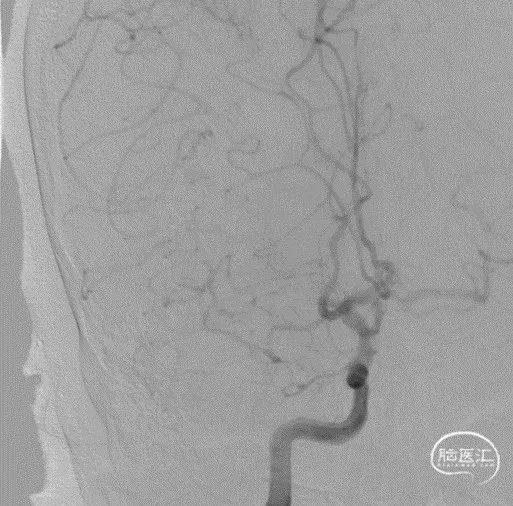

脑血管造影:右侧大脑中动脉M1段闭塞,代偿不足。

左椎动脉V4段重度狭窄。